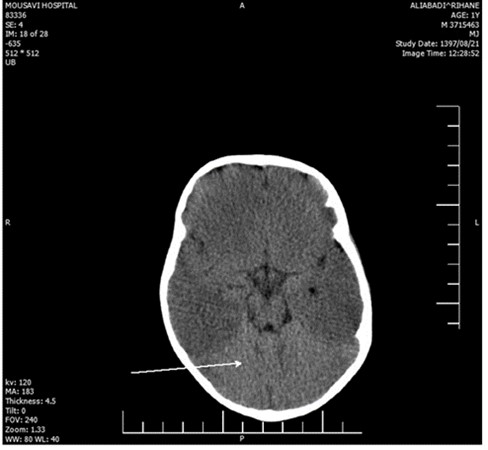

The laboratory evaluations indicated mild anemia; her CSF, ESR, CRP, CXR, and echocardiography were within the normal range. Brain CT investigation and MRI analysis of the brain indicated brain edema and hypersignality, respectively (Figure 1 - 2). Furthermore, EEG showed diffused low-voltage slow waves due to encephalopathy.

Figure 2. The MRI analysis of the brain